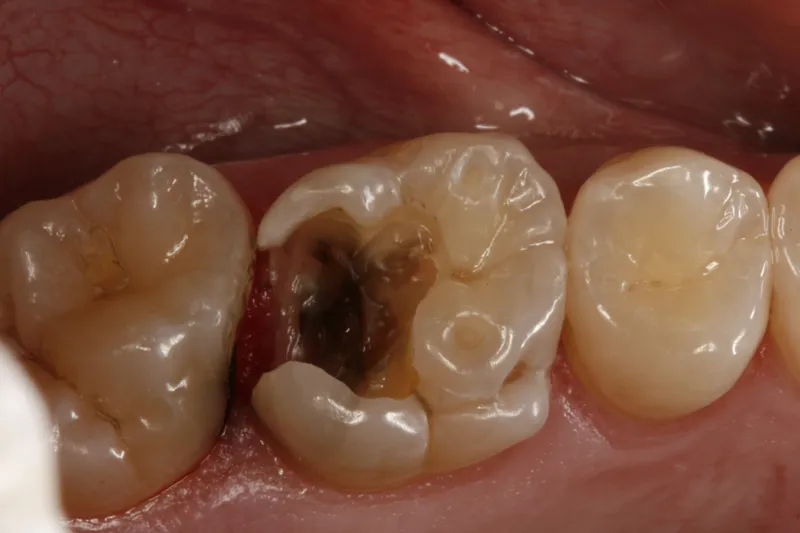

Det er et problem, at unge udskrives med lakerede, ret dybe, okklusale cariesangreb, som kommuner hævder er behandlet tilstrækkeligt

Det er et problem, at unge udskrives med lakerede, ret dybe, okklusale cariesangreb, som kommuner hævder er behandlet tilstrækkeligt med henvisning til den nævnte vejledning, der som nævnt er uden forbehold. Denne praksis har naturligvis rod i sparehensyn. I stedet for at fissurforsegle de fleste molarer i frembrud profylaktisk så forsegles kun den andel, der har udviklet dentincaries.